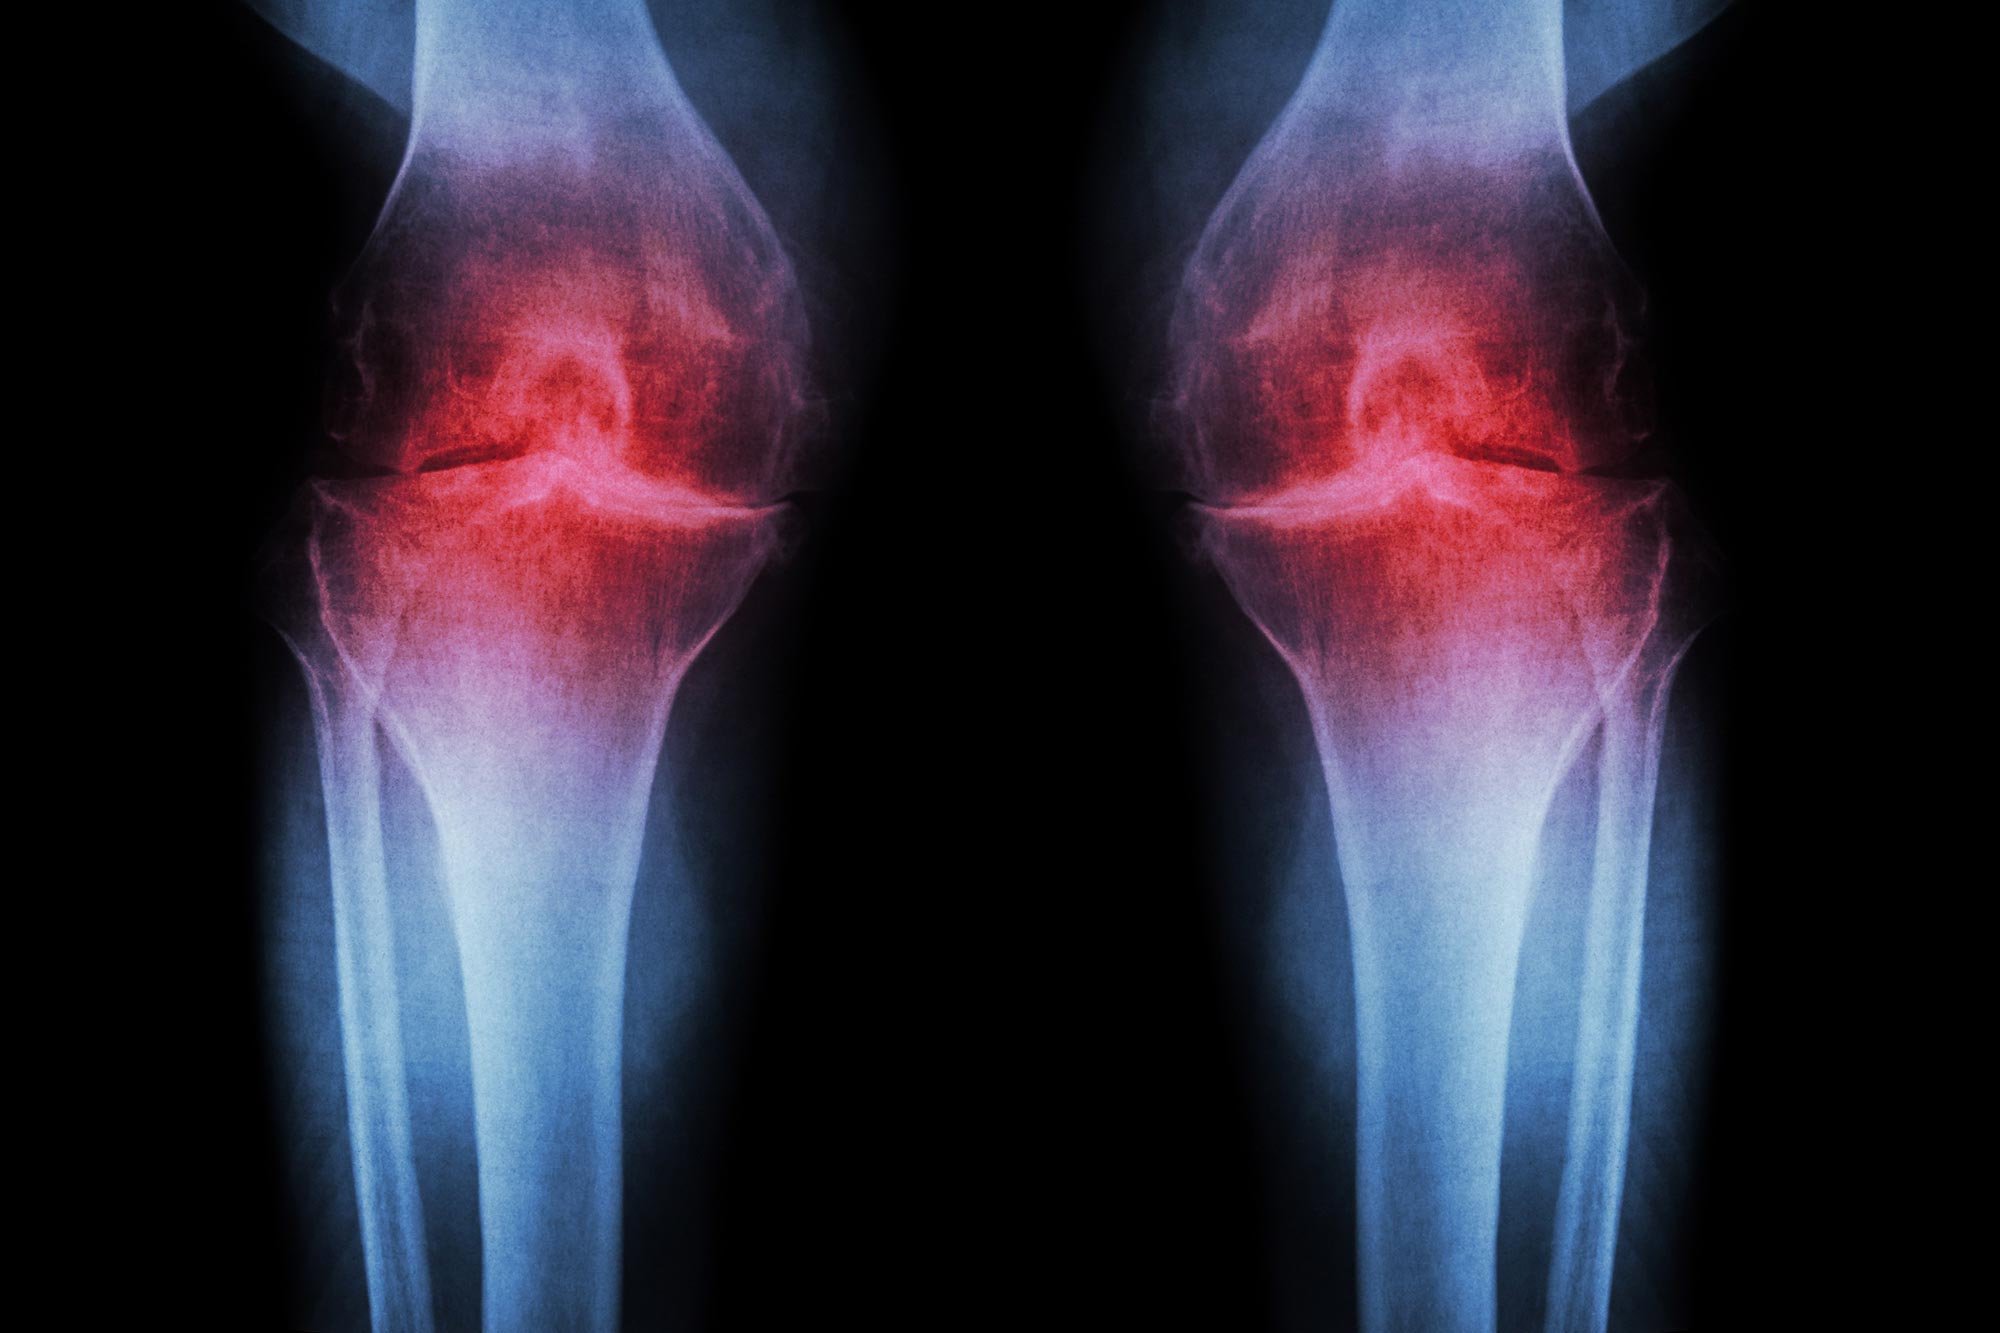

Arthritic diseases include rheumatoid arthritis and psoriatic arthritis, which are autoimmune diseases; septic arthritis, caused by joint infection; and the more common osteoarthritis, or degenerative joint disease. Arthritis can be caused from strains and injuries caused by repetitive motion, sports, overexertion, and falls. Unlike the autoimmune diseases, osteoarthritis largely affects older people and results from the degeneration of joint cartilage. Other forms are discussed below.

The various types of arthritis can be distinguished by the pace of onset, the age and sex of the patient, the amount of (and which) joints affected, additional symptoms such as psoriasis, iridocyclitis, Raynaud's phenomenon, and rheumatoid nodules, and other clues.Blood tests and X-rays of the affected joints are often performed to make the diagnosis. X-rays can show erosions or bone appositions.